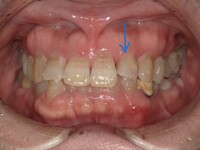

歯科治療の恐ろしさは、少しでも手を抜くと、積み重ねてきた治療効果が全て0=ゼロになってしまうことです。当院では一つ一つの治療過程にベストを尽くすべく、開業当初よりマイクロスコープ、セファロ分析や口腔内スキャンなど最新の機材を取り揃えて、幅広く、深い治療を追求してきました。

私はこれまでの歯科医師人生で、虫歯や歯周病、歯の根にある神経の処置である根管治療、入れ歯、インプラント、美容診療など、幅広く取り組んでまいりました。例えば虫歯治療では、痛みのある歯だけでなく、噛み合わせなどお口の中を総合的に考えたアドバイスや立案をし、歯を長持ちさせる処置を提供することを心がけています。